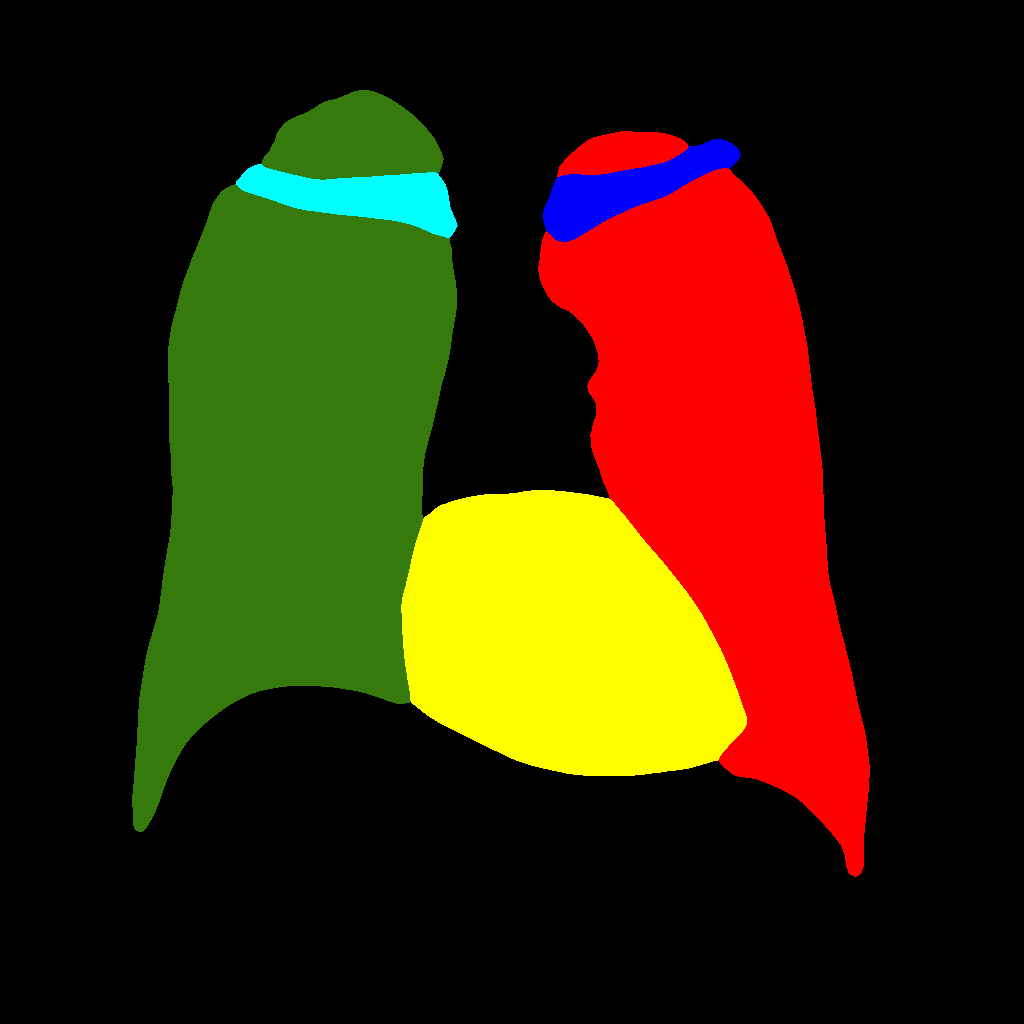

It consists in further subdividing the generation procedure, with a first phase consisting in generating the position and type of the objects that will be generated later, regardless of their shape or appearance. This is obtained by generating label–maps that contain “dots” in correspondence with different anatomical parts (lungs, heart, clavicles). The dots can be considered as “seeds”, from which, through the subsequent steps, the complete label–maps are realized (second phase). Finally, in the last step, chest X–ray images are generated from the label–maps. The exact procedure is described in the following. Initially, label–maps containing “dots”, with a specific value for each anatomic part, are created. The position of the “dot” center is given by the centroid of each labeled anatomic part. The label–maps generated in this phase have a low resolution (), as a high level of detail is not necessary, being the exact object shapes not defined — but only their centroid positions. It should be observed that this also allows to significantly reduce the computational burden of this stage and speedup the computation. The generated label–maps must be subsequently resized to the original image resolution — required in the following stages of generation (a nearest neighbour interpolation has been used to maintain the original label codes) — and translated into labels, which will be finally translated into images, using Pix2PixHD (see Figure 3).

Figure 5 and Figure 6 display some examples — randomly chosen from all the generated images — of the label–maps and the corresponding chest X–ray images generated with the three methods described in Section 3, using the FULL_DATASET and the TINY_DATASET, respectively. We can observe that, with the single and two–stage methods, the images tend to be more similar to those belonging to the training set. For example, in most of the generated images there are white rectangles, which resemble those present in the training images, used to cover the names of both the patient and the hospital. Instead, the three–stage method does not produce such artifacts, suggesting that it is less prone to overfitting.